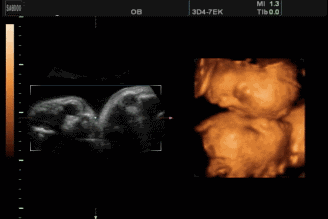

双胞胎,头对头好有爱

以后长大了也要一直友爱下去哦!